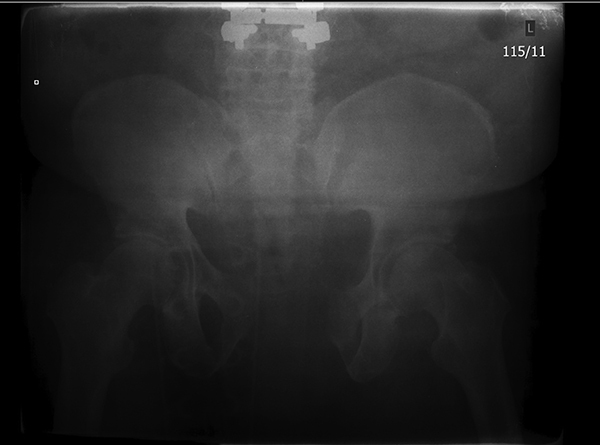

Figure 1. Patient with APC2 Fracture |

There is pubic diastasis of more than 2.5 cm and there is anterior widening of the SI joint. Source: Uzcategui M, Menaker J. Blunt pelvic trauma. Trauma Reports 2014;15:6. |